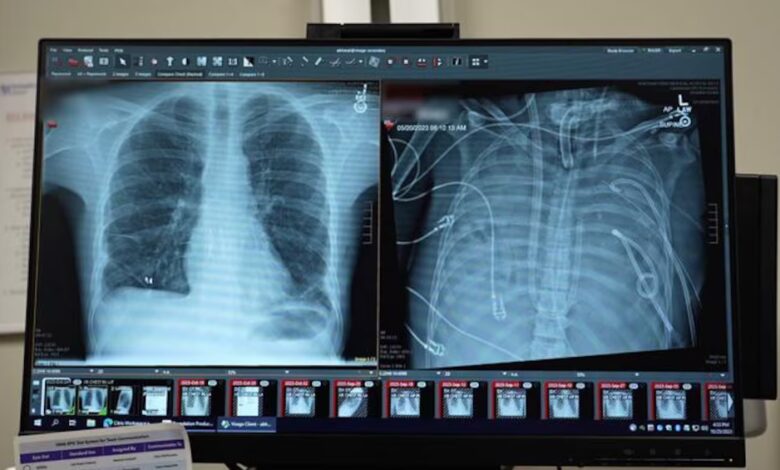

El paciente, de 33 años, permaneció dos días sin órganos respiratorios naturales, bajo monitoreo constante (Northwestern Medicine)“El corazón se detuvo apenas llegó. Tuvimos que practicarle RCP”, recordó Ankit Bharat. La infección había destruido los pulmones hasta el punto en que, según el equipo médico, estaban literalmente “derritiéndose”.

Durante 48 horas, el paciente permaneció sin pulmones, con el tórax vacío y conectado únicamente al sistema artificial. El equipo médico vigiló de cerca su evolución y, al confirmarse la mejoría, logró ingresar al paciente en la lista de trasplantes. Dos días después, se realizó el trasplante doble de pulmón. Más de dos años después del procedimiento, el paciente mantiene una vida normal y sus pulmones funcionan correctamente.